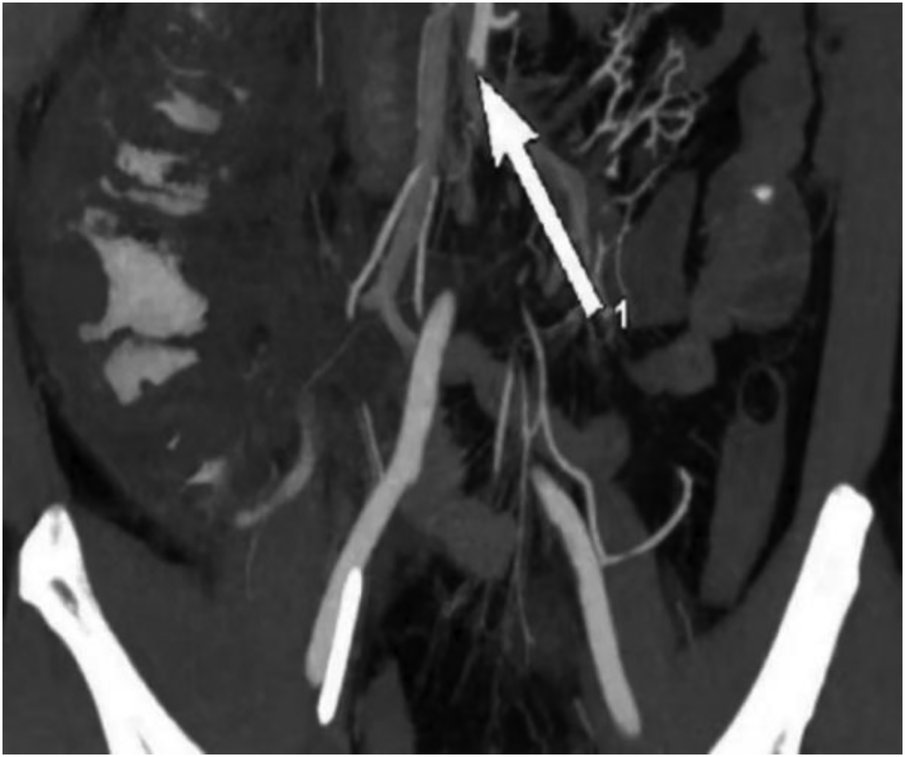

After the second procedure, the patient’s bowel movements and ventilation improved, along with an improvement in urine output. However, the patient continued to experience abdominal pain and abdominal distension without any intestinal sound. The total bilirubin level reached its highest level of 46.81 mmol/L. The intra-abdominal pressure gradually decreased to 5.5 cmH2O on the 17th day and quickly increased to 9.2 cmH2O on the 20th day. The patient has feces every day, ranging from 200 ml to 600 ml per day, but on the 20th day, he began to have bloody stool. Additionally, symptoms of peritonitis and signs of shock were observed. The second CTA suggested signs of intestinal necrosis, which needed an urgent surgical intervention to evaluate the extent of the necrosis and potentially remove any nonviable tissue. (Figure 3).

Figure 3

Abdominal artery embolism and signs of partial colon necrosis with inflation (arrow).